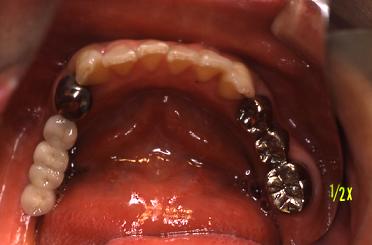

【症例 1】右下奥歯3本欠損 (41才,女性)

術前

右下奥歯3本の歯がないです